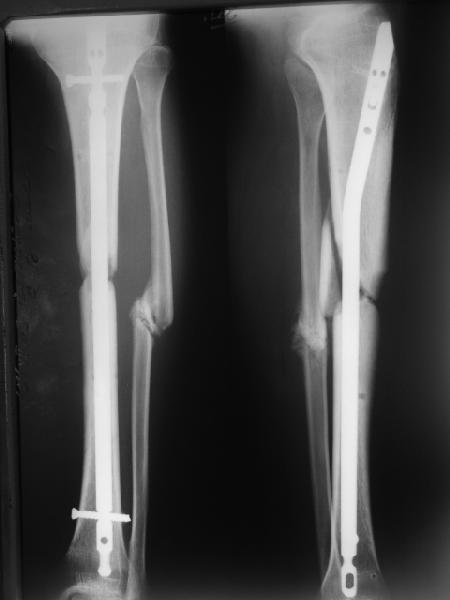

Вот пример, тоже открытый перелом, первичный дефект, пробыл в аппарате 5 мес. Титановый гвоздь, сразу динамический, без покрытия. Больше не делали ничего.